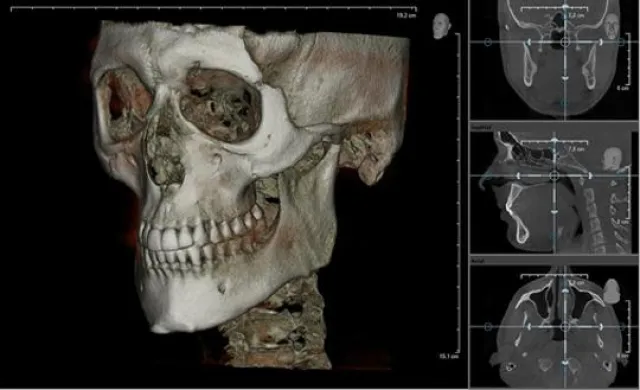

Die 3D-Diagnostik und Planung im umfassenden Gebiet der Zahnheilkunde gewinnt in zukunftsorientierten Praxen immer mehr an Bedeutung. Zumal sie mit ihrer minimalen Strahlenbelastung ein präzises, dreidimensionales Abbild der zu behandelnden Region liefert und somit dem Operierenden eine OP-Planung ohne Überraschungen ermöglicht. Für eine umfassende Fortbildung im DVT-Bereich engagiert die Rheinfels-Akademie wiederholt Prof. Dr. Uwe Rother (Facharzt Radiologie DVT) als DVT-Spezialisten. Im zweiteiligen DVT-Spezialkurs am 12. März und 18. Juni erweitern Zahnärzte ihre Kompetenz, um ein eigenes DVT-Gerät in ihrer Praxis betreiben zu können. Inhalte der praxisbezogenen Fortbildung sind neben dem Stellenwert und dem Einsatz der digitalen Volumentomographie auch das Aufzeigen der Möglichkeiten und Grenzen bei der Erkennung von Raumforderungen anhand von CD-Demonstrationen. Rother analysiert gemeinsam mit den Zahnärzten Fallbeispiele und stellt differentialdiagnostische Überlegungen zum DVT-Einsatz an.

Nach bestandener Prüfung erhalten die Zahnmediziner die offizielle Befähigung zur Aufnahme und Befundung dreidimensionaler Röntgenbilder (DVT), auch anwendbar ohne eigenes Gerät in der Praxis. Ebenso erwerben sie die Aktualisierung der Fachkunde im Strahlenschutz für die nächsten fünf Jahre. Teilnehmer erhalten 23 Fortbildungspunkte nach den Richtlinien der BZÄK und DGZMK.